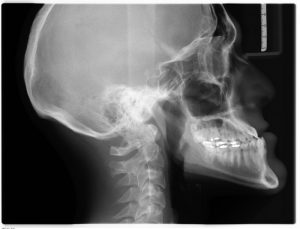

Røntgenundersøgelse

01 december 2025